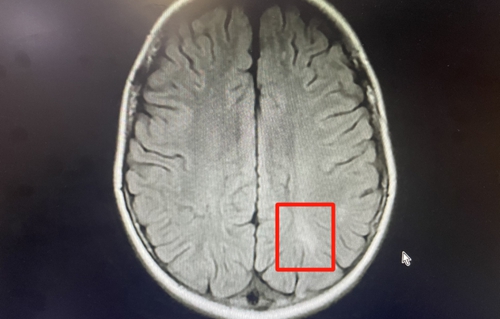

△照片來源于神經(jīng)內(nèi)科。秋秋顱內(nèi)有異常信號,左眼視神經(jīng)相比右眼明顯腫脹

神經(jīng)內(nèi)科接診醫(yī)生完善了頭顱磁共振檢查,提示秋秋顱內(nèi)有異常信號,高度懷疑中樞神經(jīng)系統(tǒng)炎性脫髓鞘疾病。

收入病房后,經(jīng)過進一步對癥化驗、檢查,確診孩子患有中樞神經(jīng)系統(tǒng)炎性脫髓鞘疾病,而引起脫髓鞘的原因是“MOG抗體相關疾病”。